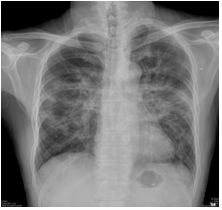

16. 二十八歲男性病患,過去身體健康。因為發燒、血便和右上腹痛多日住院。糞便例行檢查潛血4+。大腸內視鏡檢和病理學查如圖A及圖B所示;腹部電腦斷層如圖C所示。請問下列敘述何者為是? (A) 最有可能的診斷為Klebsiella pneumoniae菌血症和肝膿瘍,應即刻在超音波導引下進行抽取和投與ceftriaxone。 (B) 顯微鏡檢具有高達95%的敏感度和特異性分別出致病原。 (C) 該疾病並非法定傳染病,不需通報。 (D) 最好的治療是metronidazole或tinidazole。 (E) 十天左右的抗生素即可完治,並不需清除腸腔內病原。